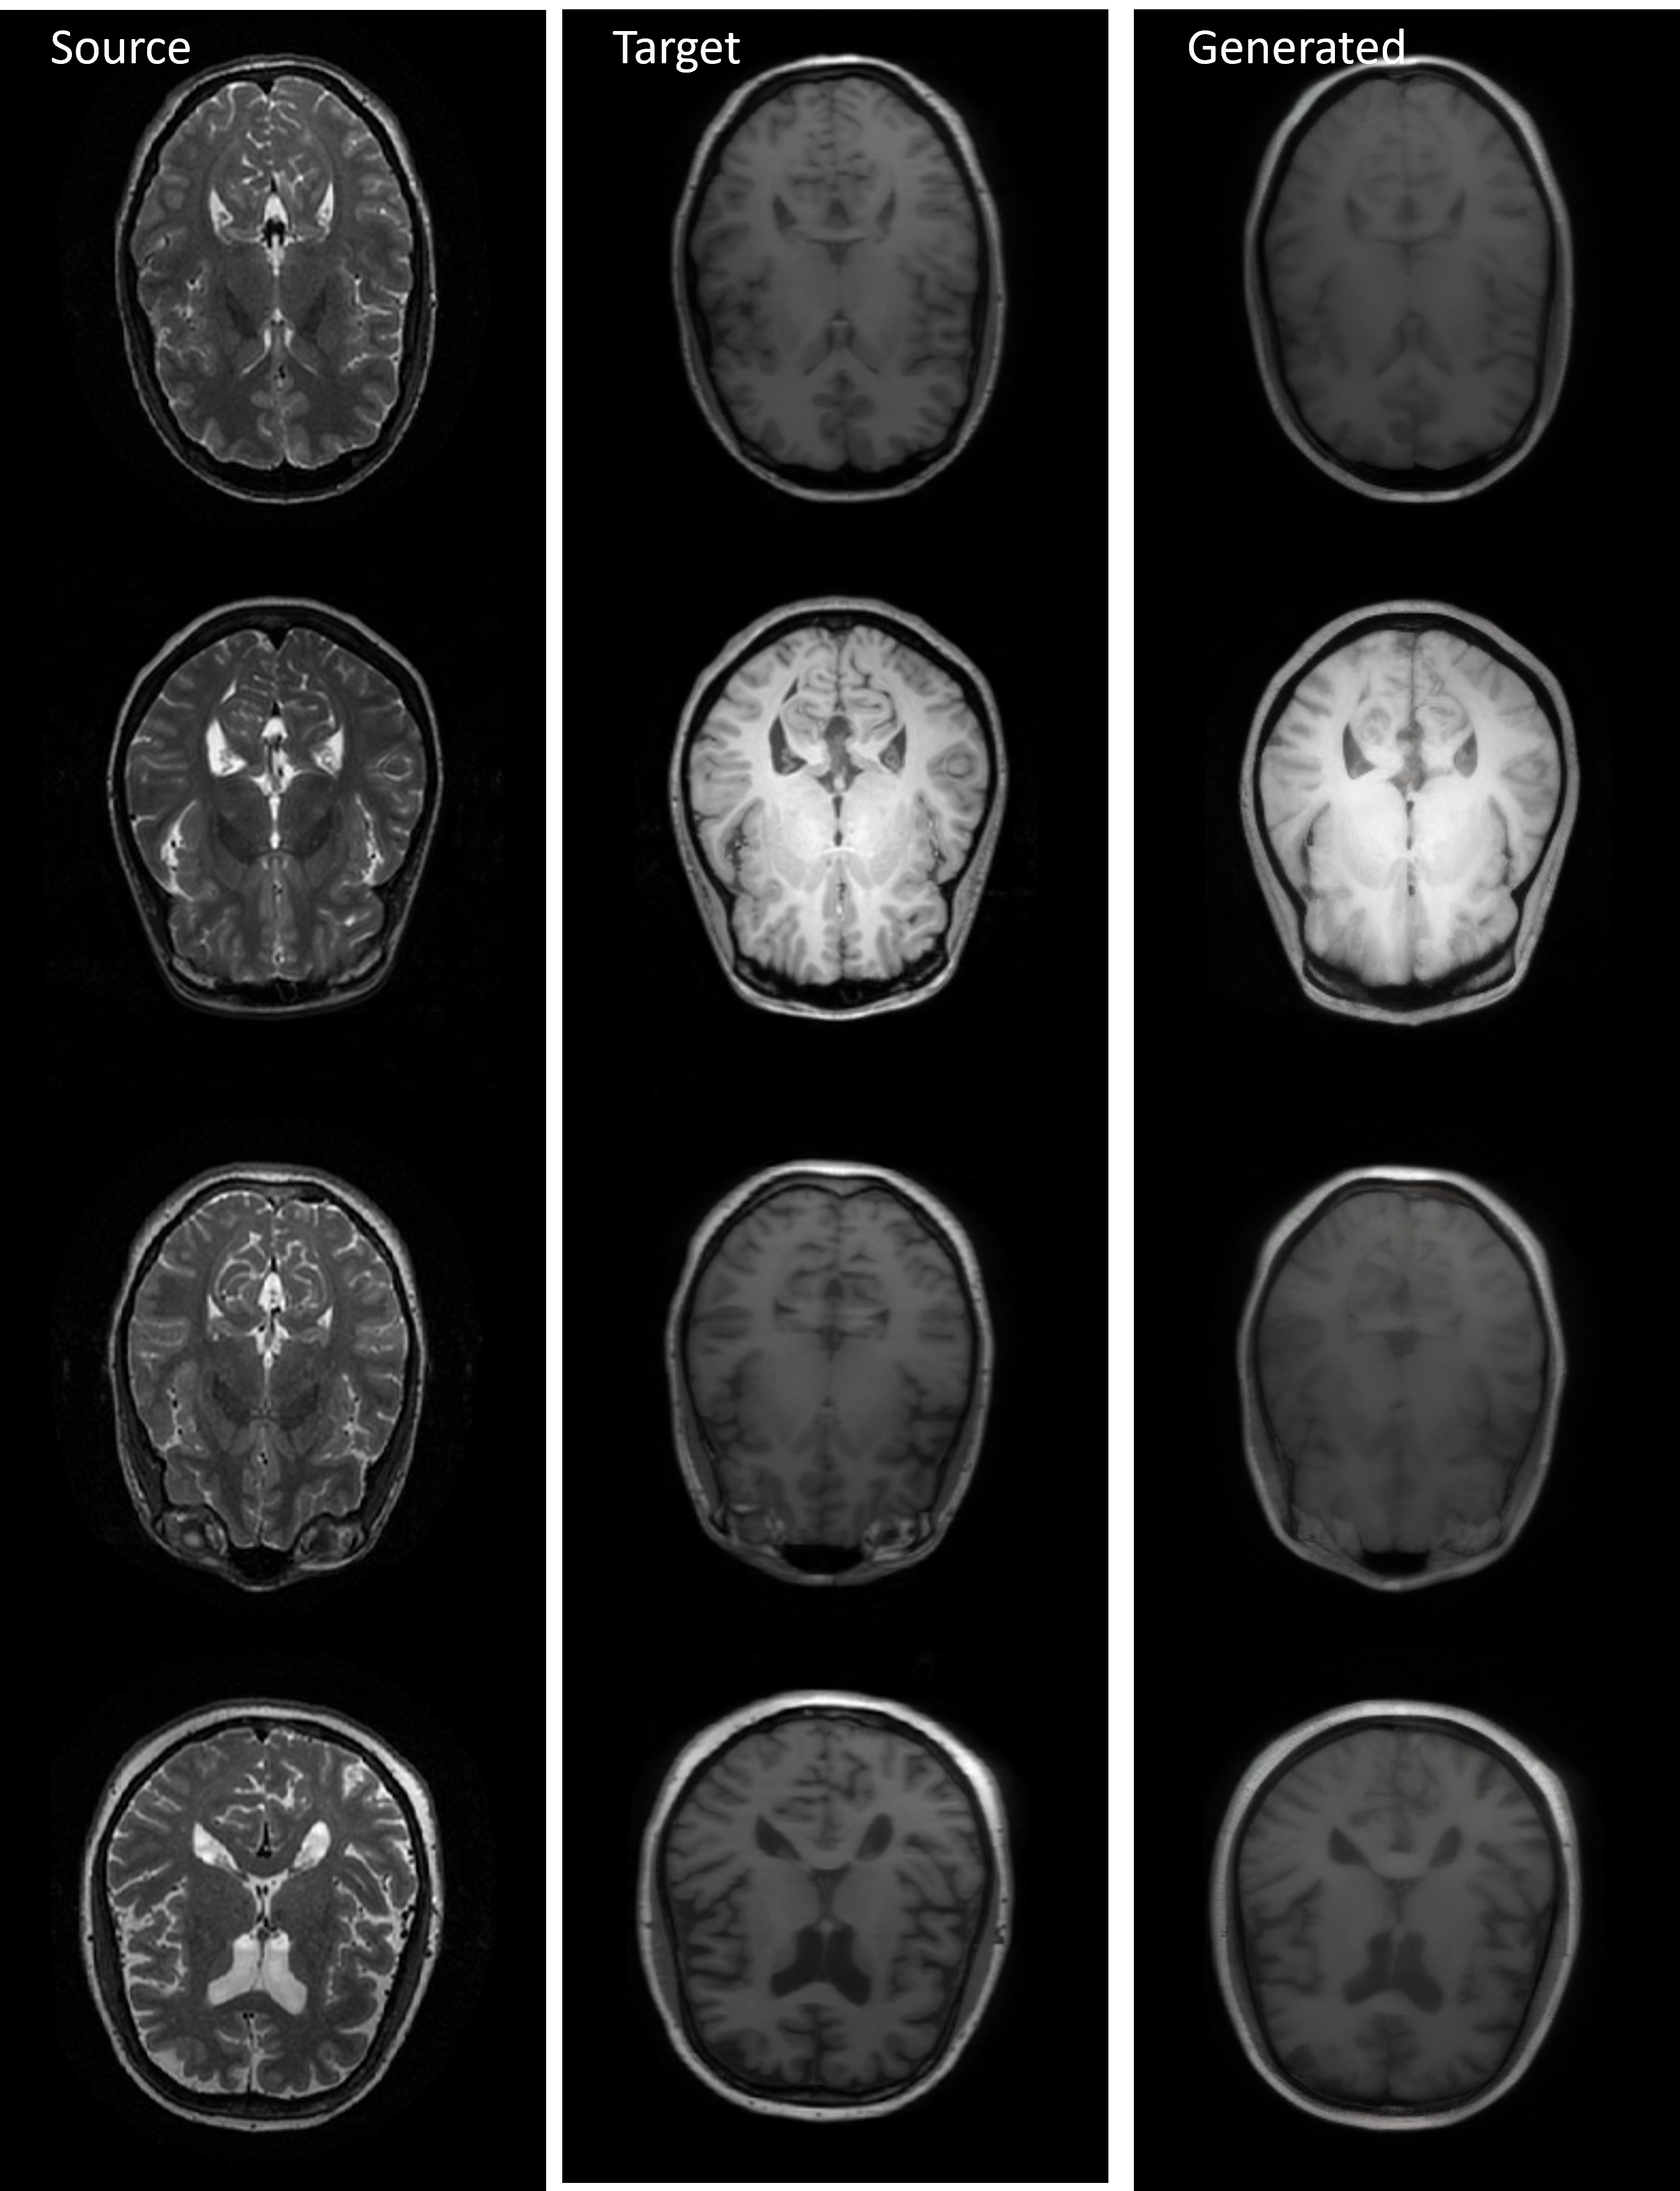

Refer to caption

Figure 2: Visual comparison across three cross-modal tasks: IXI medical conversion, Sentinel SAR-to-optical, and PSCDE semantic mask. (See more in Appendix 6.15).

IXI & Sentinel Datasets: Fig. 2 shows that on IXI, CDTSDE reconstructs anatomically coherent images with crisp cortical and ventricular boundaries. It improves over DOSSR, which slightly smooths details, and clearly surpasses Pix2Pix and the bridge-based methods (DBIM, ABridge, BBDM), which exhibit blur, noise, or partial structural collapse. On Sentinel (SAR\rightarrowOPT), CDTSDE produces semantically aligned, natural optical images with stable geometry, while DOSSR loses fine detail, Pix2Pix exaggerates colors and textures, and the bridge-based methods leave fragmented or inconsistent patterns even when DBIM locally improves contrast.